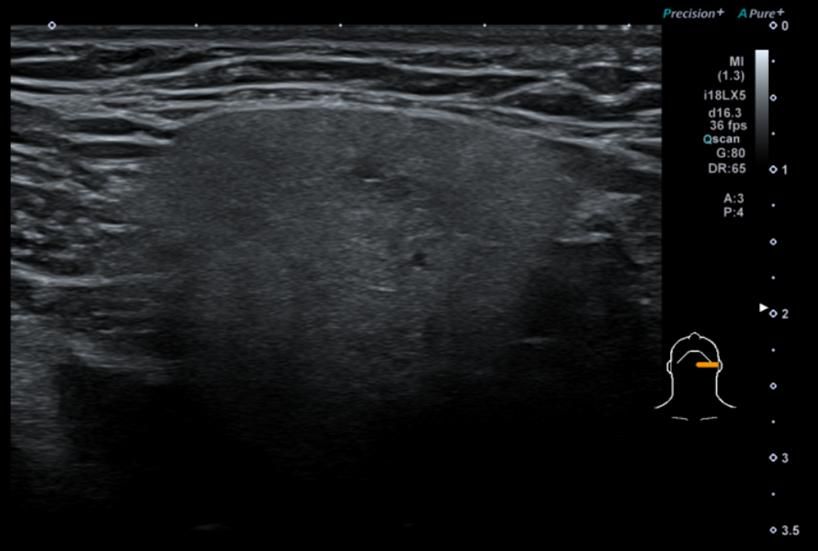

• 4번 째 사진